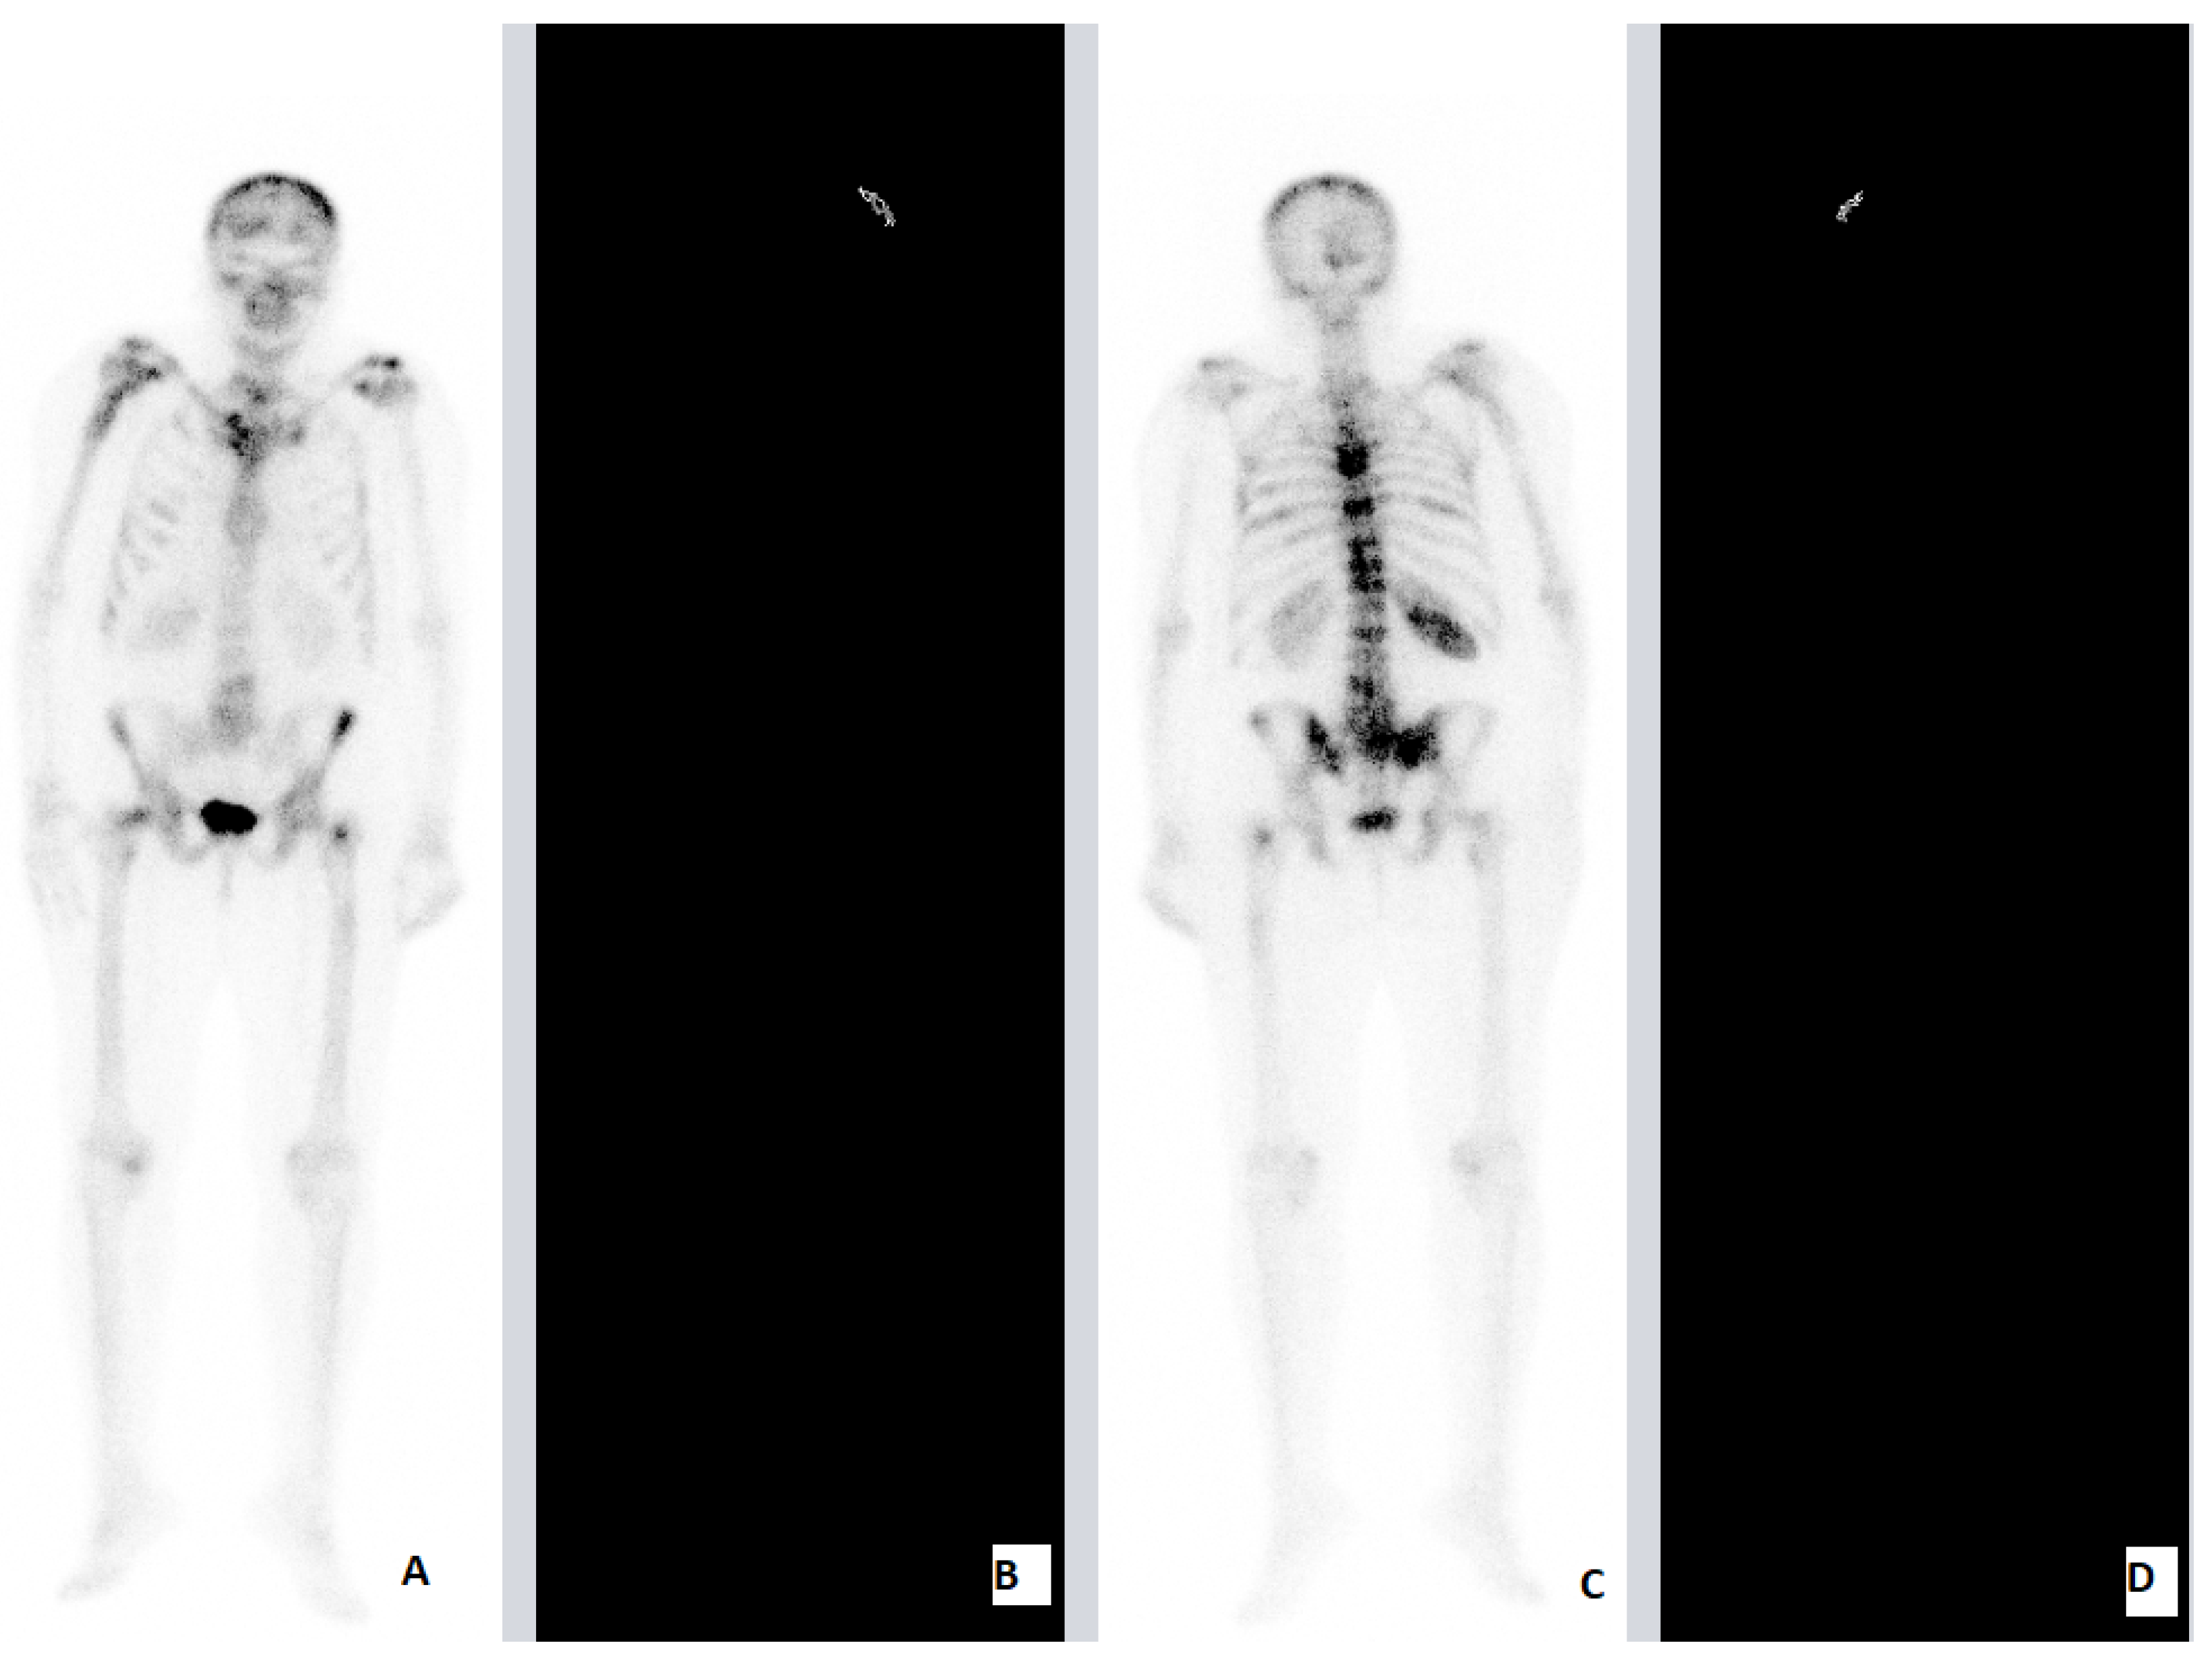

| PCa | 84 | M | HFRT | 20 Gy (4 Gy) | 7th, 8th, 9th, 10th TV Stn Lhs Tb Rhs Tb | 7th, 8th, 9th, 10th TV | ADT | Concomitant | Stn Lhs Tb Rhs Tb | 2 | 5 |

| PCa | 72 | M | HFRT | 20 Gy (4 Gy) | 11th TV Lhs Fmr Rhs Fmr Lhs Hmr Rhs Hmr | 11th TV Lhs Fmr Rhs Fmr | ADT | Concomitant | Lhs Hmr Rhs Hmr | 2 | 6 |